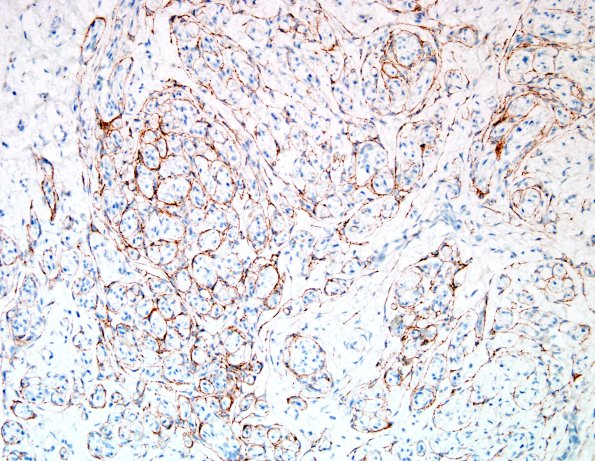

4D6,7 These are typical mini-fascicles tightly surrounded by perineurium. (EMA IHC)